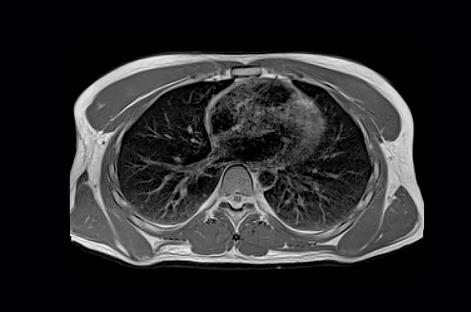

空気と組織の境界では、磁化率*2の大きな差により信号強度が著しく低下するため、高磁場MRIでは肺の検査が難しいのが現状だ。新しい磁場強度0.55テスラでは、磁化率アーチファクトが少ないため、肺のイメージングを改善し、新しい臨床応用を可能にする。